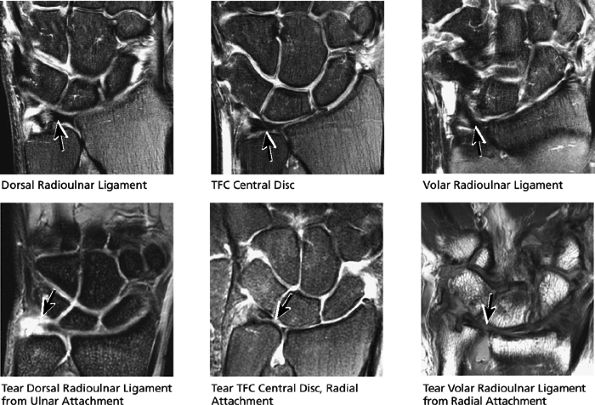

The dorsal radioulnar ligament and palmar radioulnar ligament are the primary ligamentous stabilizers of the distal radioulnar joint and on axial plane images are seen coursing on both the dorsal and volar sides of the TFC, at the level of the base of the ulnar styloid, where the ligaments insert. Tears of the dorsal radioulnar ligament are associated with volar subluxation of the ulna. Tears of the volar radioulnar ligament are associated with dorsal subluxation of the ulna. Distal radioulnar joint instability is suggested when the ulnar head is abnormally subluxed or dislocated with respect to the radius, beyond the normal range of motion allowed for pronation and supination. In addition to ligamentous injury, osseous injuries such as fractures at the base of the ulnar styloid also may lead to distal radioulnar joint instability.

![]() |